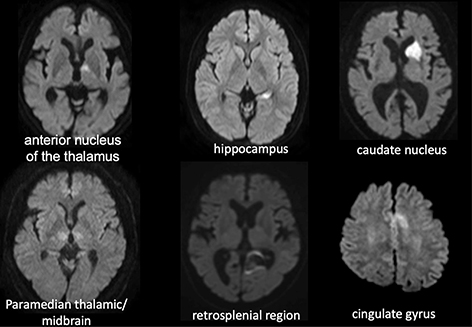

Fig 4

Figure 4. Lesions in patients with episodic memory impairment. Memory impairment occurs when strokes occur in areas associated with episodic memory, including the hippocampus, anterior thalamic nucleus, medial papillary nucleus, parahyppocampal gyrus, amygdala, medial thalamic nucleus, and orbitofrontal cortex.

The neural circuits related to episodic memory include the Papez circuit (medial limbic circuit) centred around the hippocampus, anterior thalamic nucleus, medial mammillary nucleus, and parahippocampal gyri, as well as the Yakovlev circuit (ventrolateral limbic circuit), centred on the amygdala, medial thalamic nucleus and orbitofrontal cortex. Although each circuit is independent of the other (6), they are very closely related (Figure 3), and cerebral haemorrhage or cerebral infarction at these sites manifests as memory loss (Figure 4).

The manifestation of memory loss associated with medial temporal lobe lesions is variable. The hippocampus does not store or retrieve memory; instead, it plays an important role in encoding memory and is involved in consolidating memories formed within the recent past (7). Damage localized to the hippocampus presents as anterograde amnesia, but is not always associated with retrograde amnesia, and old memories are often retained (8). Widespread damage to the medial aspect of the temporal lobe, such as the hippocampus and parahippocampal gyrus, impairs retrieval of old memories and results in severe backward amnesia (9).

The posterior cingulate gyrus has fibrous connections with the anterior cingulate gyrus, medial aspect of the temporal lobe, prefrontal cortex, posterior parietal lobe, thalamus, and caudate nucleus. Even lesions in the retrosplenial region present with memory loss, known as retrosplenial amnesia, which is thought to be caused by impairment of the fibrous communication of the memory circuit between the hippocampus and the anterior nucleus of thalamus due to damage to the posterior cingulate gyrus (10). It reportedly occurs more frequently as a sequela of hemorrhage than that of infarction (11, 12).

The thalamus receives vascular supply from the anterior and posterior circulation (13). The thalamotuberal arteries (polar artery) that branch from the posterior communicating artery perfuse the anterior nucleus of thalamus, and damage to this area presents as episodic memory loss. The paramedian thalamic artery, which originates from the posterior cerebral artery, traverses the dorsomedial nucleus of thalamus, and may also branch bilaterally from the posterior cerebral artery on one side (14). Lesions of the bilateral dorsomedial nucleus of the thalamus can result in severe impairment of consciousness. Damage to these areas of the thalamus due to cerebral infarction, surgical invasion (15), and/or cerebral hemorrhage (16) causes memory loss (Figure 5).